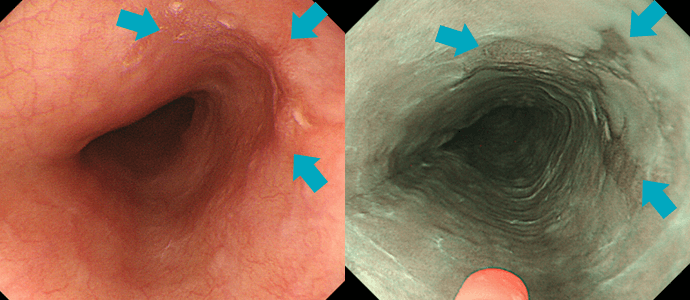

当院で採用している内視鏡システムであるEVIS X1は、高精細画像での撮像ができるだけでなく、狭帯域光観察(narrow band imaging, NBI)の性能も非常に高いものとなっているため、通常発見しにくいような早期のがんなどの病変も明瞭に描出することができるようになっています。

通常光(白色光)観察ではやや不明瞭な早期胃がん病変ですが通常光(白色光)観察ではやや不明瞭な早期胃がん病変ですが

NBI観察では明瞭化しています。NBI観察では明瞭化しています。